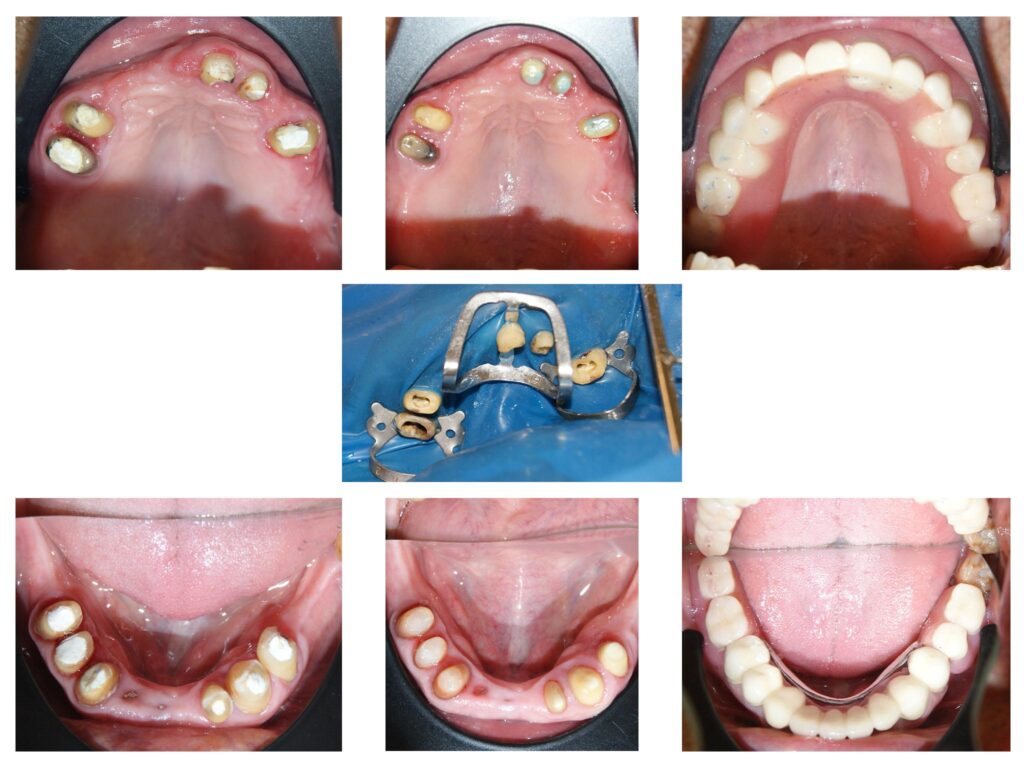

Reabilitare orală complexă cu redimensionarea dinților cu grad accentuat de uzură. A fost necesară o soluție de provizorat de 6 luni de zile în care am verificat dacă pacientul se poate adapta cu înălțarea ocluzală propusă de noi. Am realizat tratamente de canal și reconstituiri atât pentru înălțarea dinților, cât și pentru tratarea proceselor infecțioase active. Rezultatele sunt remarcabile atât din punct de vedere funcțional cât și estetic